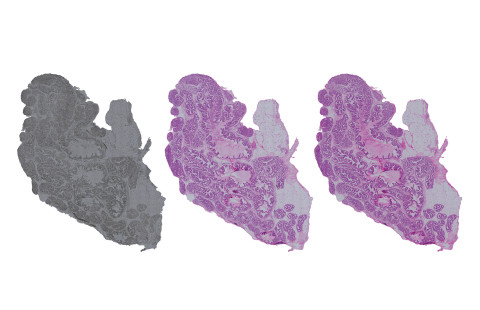

The new artificial intelligence method produces computational images that very closely resemble those produced by the actual chemical staining process.